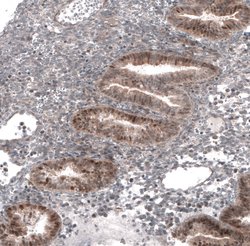

The basic helix-loop-helix transcription factor TCF21/Pod1 (also called capsulin or epicardin) is involved in kidney, lung and spleen organogenesis. It is also essential for normal development of the testes and ovaries. TCF21/Pod1 is involved in the transcriptional repression of steroidogenic factor 1 (Sf1/Nr5a1/Ad4BP), an orphan nuclear receptor that regulates the expression of multiple genes (including Scc) that mediate sexual differentiation.

| Immunohistochemistry, Western Blot | |